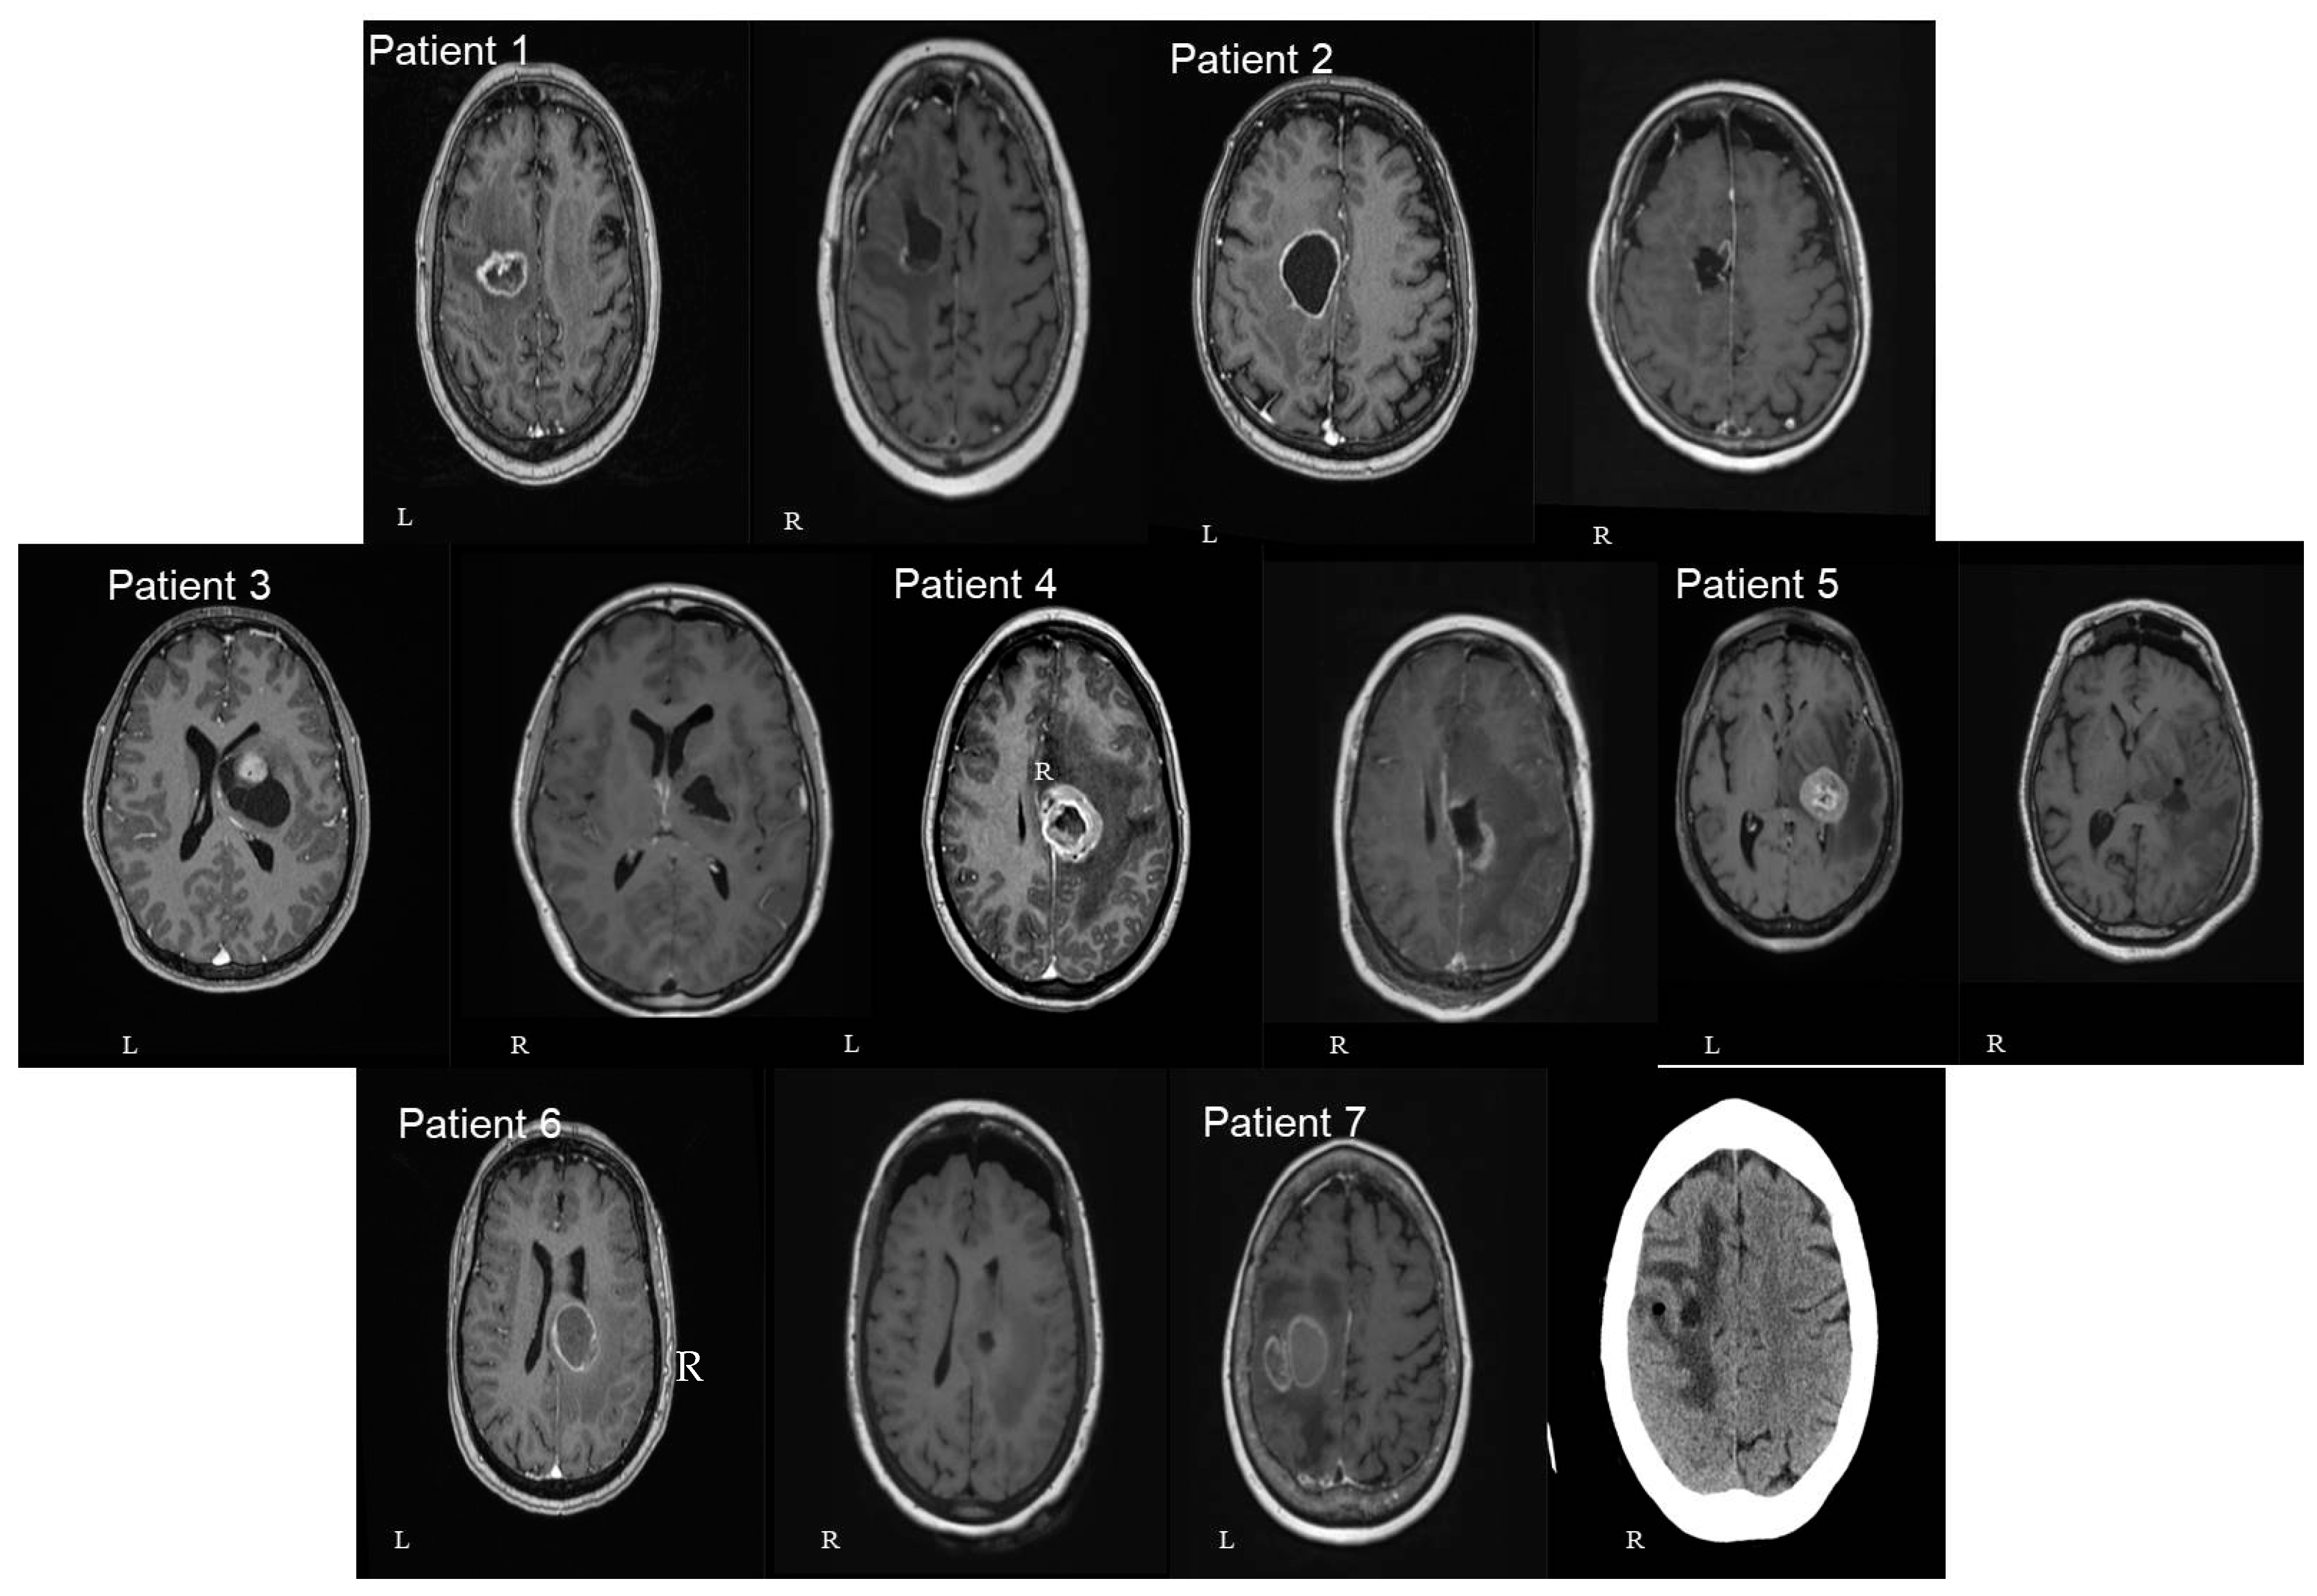

Figure 4.

Axial (left—L) and sagittal (right—R) T1 gad MRI brain images of all seven patients included in our study. In 3 patients the lesion was located at the cingulate gyrus (numbers 2, 4, and 6). In 2 of them, the tumor was centered in the precentral gyrus (numbers 1 and 7). In the final 2 patients, the lesion was centered at the basal ganglia involving the thalamus and the internal capsule (numbers 3 and 5). The number of patients in each image corresponds to the patients mentioned in Table 1.

In three patients the lesion was located at the cingulate gyrus. In two of them, the tumor was centered in the precentral gyrus, and in the final two, at the basal ganglia involving the thalamus and the internal capsule. Four patients had left-sided lesions and three had right-sided lesions. The mean distance between the lesions and the cortex as measured in the preoperative MRIs was 30.9 mm (range: 7 mm–46 mm) (Figure 3 and Figure 4). The mean volume of the included lesions was 13.2 cm3 (range: 3.3–32.6 cm3).